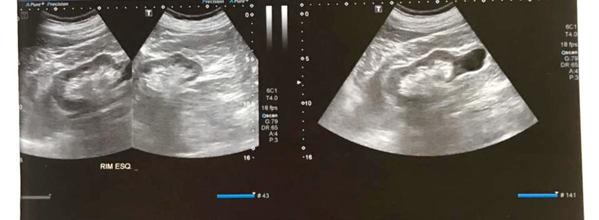

- USG – dilatação bilateral, massa vesical

- RTU da lesão em próstata e bexiga

- nova RTU de lesão